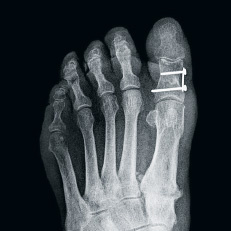

Metatarsalgien können oft auf einen Hallux valgus (hier vor und nach der Operation) zurückgeführt werden.

Bei Anna Schwegler ist die Ursache für ihre Schmerzen eine Hammerzehe mit einem zu langen zweiten Mittelfussknochen. Früher wurde bei dieser Diagnose ein Draht durch die Zehe gebohrt, der vorne herausschaute. Das hielt viele Patienten von einem Eingriff ab. Anna Schwegler hat sich zusammen mit dem Spezialisten für ein neues Operationsverfahren ent­schieden, bei dem die Schienung nicht aus einem Draht, sondern aus selbstauflösenden Zuckerstiften besteht. Damit wurden im Salem-Spital in jüngster Vergangenheit sehr gute Erfahrungen gemacht.